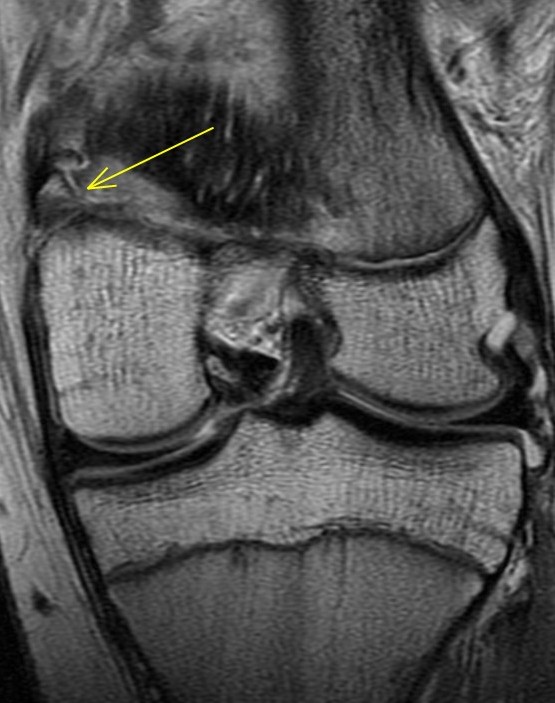

14 y/o tackled from the side after blocking a field goal in American football

The adductor magnus insertion is avulsed and there is fluid within the physis consistent with a SH injury (probable type 2 although its a bit tough to say whether the fragment was metaphyseal or epiphyseal). There was also subperiosteal blood laterally. Orthopedist saw an ossicle on plain films. Alignment good and no ACL or meniscus so he will be put in a brace and treated conservatively. Father asked if he could play in 3 weeks. I said nope.

Avulsion fracture of the adductor magnus insertion